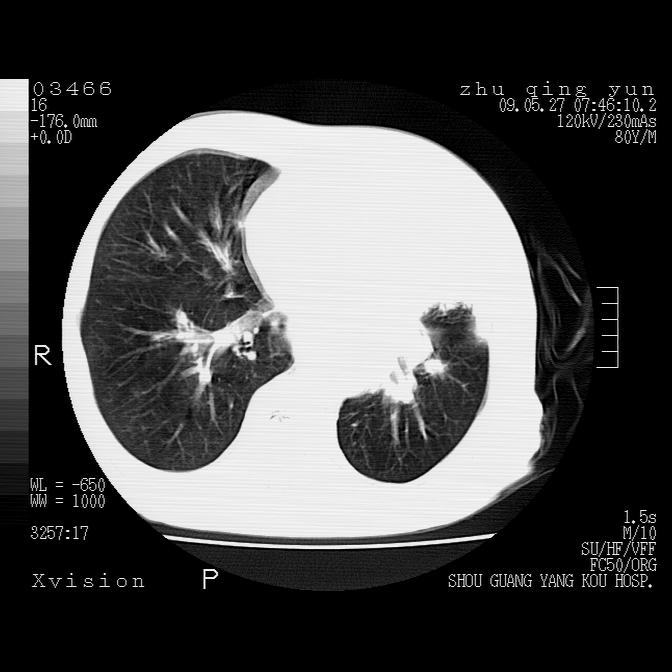

病人男性,年龄80,气喘来院,其他病史不太详细,1月前有过恶心,呕吐,在当地人民医院做过钡餐,诊断胃炎,

1)考虑左肺中央型肺癌并阻塞性肺炎,后下纵隔受侵伴纵隔淋巴结转移。2)双侧少量胸腔积液,胸膜增厚。3)心包积液。

左肺下叶见多发片状及结节状病灶,左肺基底段支气管闭塞,纵隔内见多发淋巴结肿大,纵隔向左侧移位,左侧胸廓变小。应该是左肺下叶中心型肺癌,纵隔淋巴结转移,左侧肺内转移,左肺基底段肺不张,阻塞性肺炎。

1)考虑左肺中央型肺癌并左肺下叶阻塞性肺炎、不张;左胸膜腔积液、心包积液、纵隔淋巴结转移;癌肿累及左心房。2)左心室大。冠状动脉壁钙化斑。

恶性占位是肯定的,并累及心包并纵隔淋巴结转移/左肺癌性淋巴管炎/肺部感染。是中心性或纵隔型肺癌,还是后纵隔恶性占位,还是食道中下段癌或食道受累需鉴别。